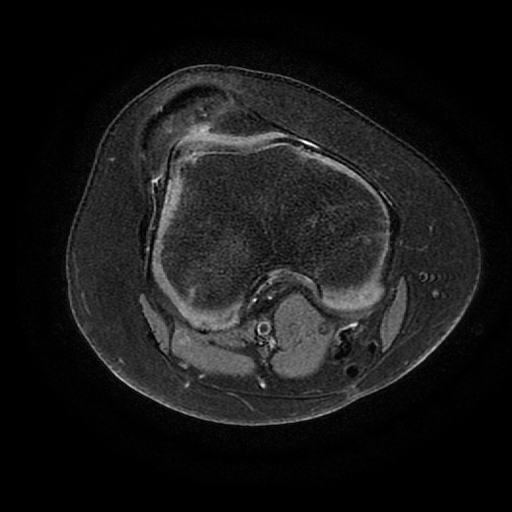

Apex patellae

Apex patellae 117 фото